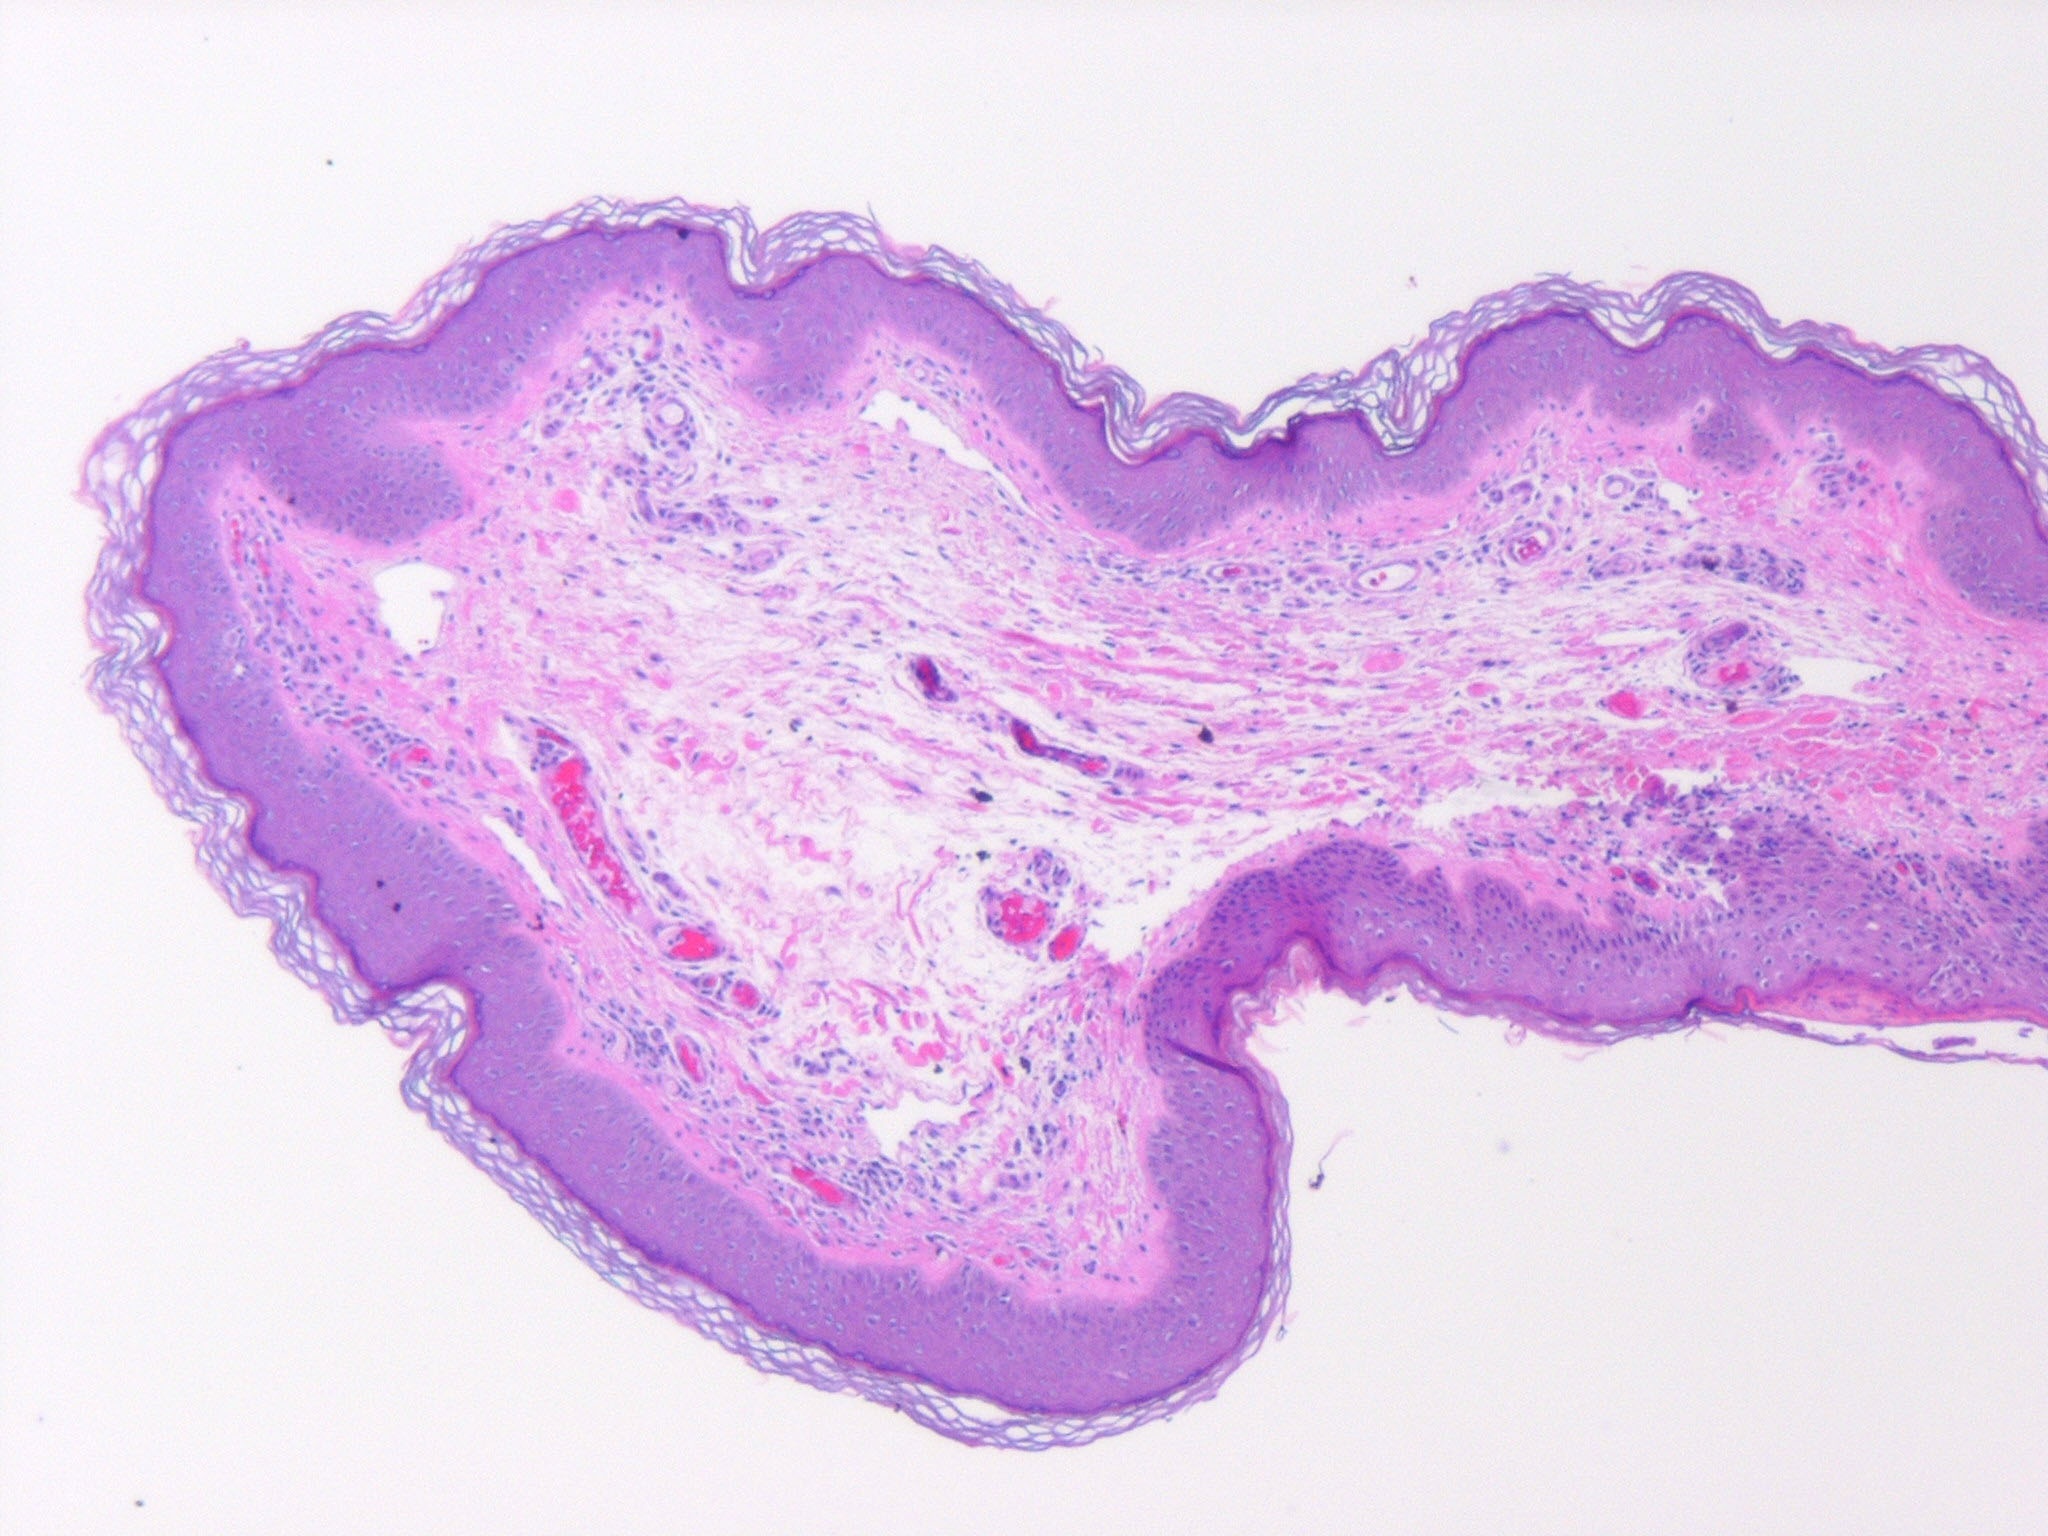

Fibroepithelial poly = البوليب الظهاري الليفي

Atlas of skin histopathology